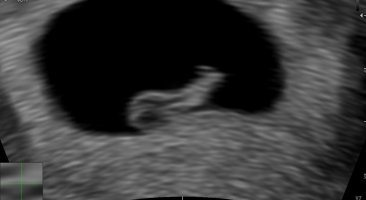

Hehe, bra! Jeg har bare erfaring med at «mest sannsynlig» stiller inn hodet på at det veldig sannsynlig er jente. Men jeg er vel litt skada etter to beskjeder om jenter der inne, og så har jeg båret tre gutter og ingen jenterJa godt tips! Men han sa han gjetter og vi bruker fortsatt «mest sannsynlig» når vi snakker om at det er jente. Selv om nubben står ganske greit på bildene xD